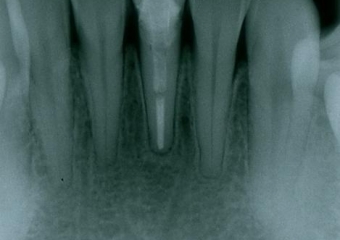

Raio x inicial

Raio x após extração e instalação do implante e dente provisório imediato